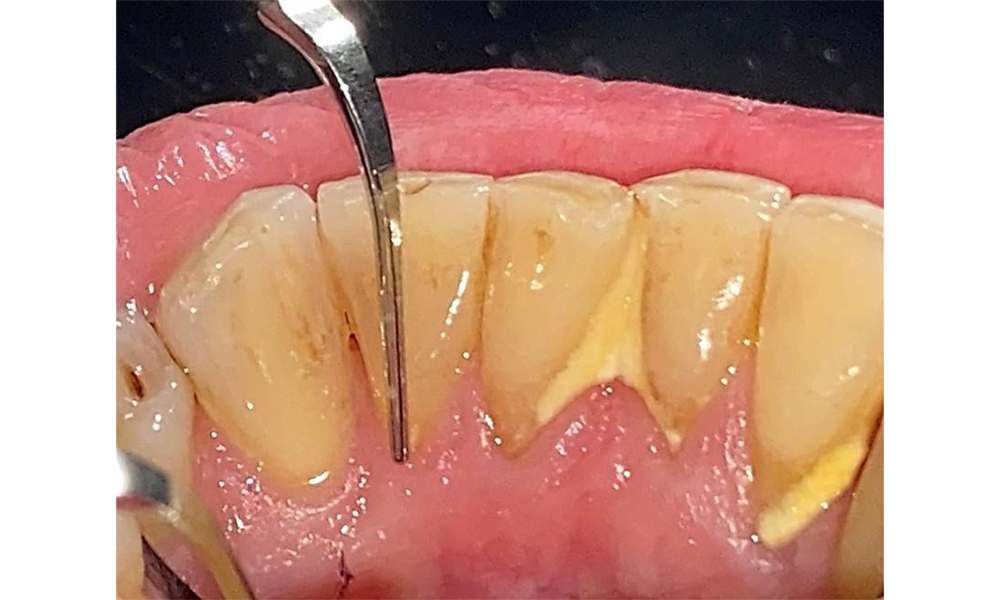

There are no limitations regarding the choice of instrumentation methods. Regular supragingival and subgingival instrumentation is essential to prevent disease progression due to the pre-existing periodontitis and high risk of recurrence. There are no limitations placed on the selection of instruments for mechanical biofilm removal from a general medical perspective, and removal should be performed as needed. Hard and mineralized plaque, such as calculus and concretions, should be removed using manual instruments or sonic/ultrasonic scalers (Fig. 9) (8, 9).

Use an ultrasonic tip to remove hard, mineralized plaque (Proxeo Ultra scaler with the Perio tip, W&H, shown here).

Fig. 9: Use an ultrasonic tip to remove hard, mineralized plaque (Proxeo Ultra scaler with the Perio tip, W&H, shown here). © Dr R. Krapf